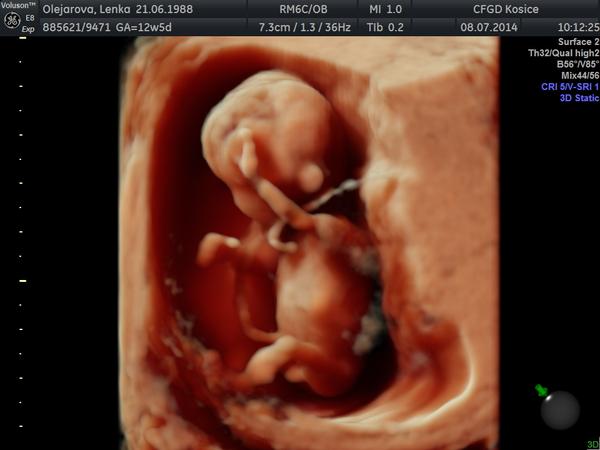

Krasne ranko bambulky, tak z nasho ducha krasneho tu mame uz podla utz 14 tt 🙂 Vcerajsie NT meranie dopadlo na jednotku, podla lekara je to chlap ako lusk, ale 1. augusta ma objednal znova na sono a na tripple testy tak povedal, ze uz to len potvrdi 🙂 teraz to bolo tak na 90 percent , ale trcalo tam cosi 🙂 pupocnik to nebol, lebo ho ma drobuliatko okolo krku 🙂 Vsetky vysledocky mame super a sme vacsi o 2 dni 🙂 tesime sa. vsetkym snazilkam drzime palusky :* drzte sa.